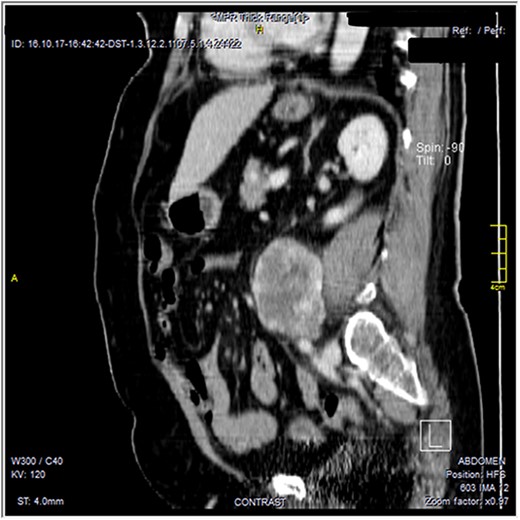

The CT scan was confirming the presence of a relatively well-defined retroperitoneal lobulated mass lesion seen extending along the left lateral wall of the distal abdominal aorta and left common iliac artery and anteromedial to the left psoas muscle. It showed heterogeneous intense peripheral enhancement during the porto-venous phase, the fat planes were preserved between the lesion and adjacent structures with no gross evidence of local invasion (Figs 1–3). The first diagnostic possibility was made as a retroperitoneal paraganglioma based on the CT appearance. The surgical decision of tumor removal was done.

Contrast-enhanced reformatted sagittal images—soft tissue window, show well-defined peripherally enhancing lobular mass lesion. Preserved fat planes around the lesion are noted with no signs of local invasion.